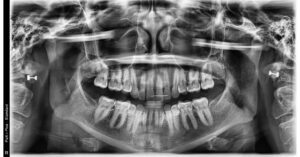

A 34- year old Caucasian female presents with a chief concern of “I don’t like my overbite and spaces between my front teeth.”